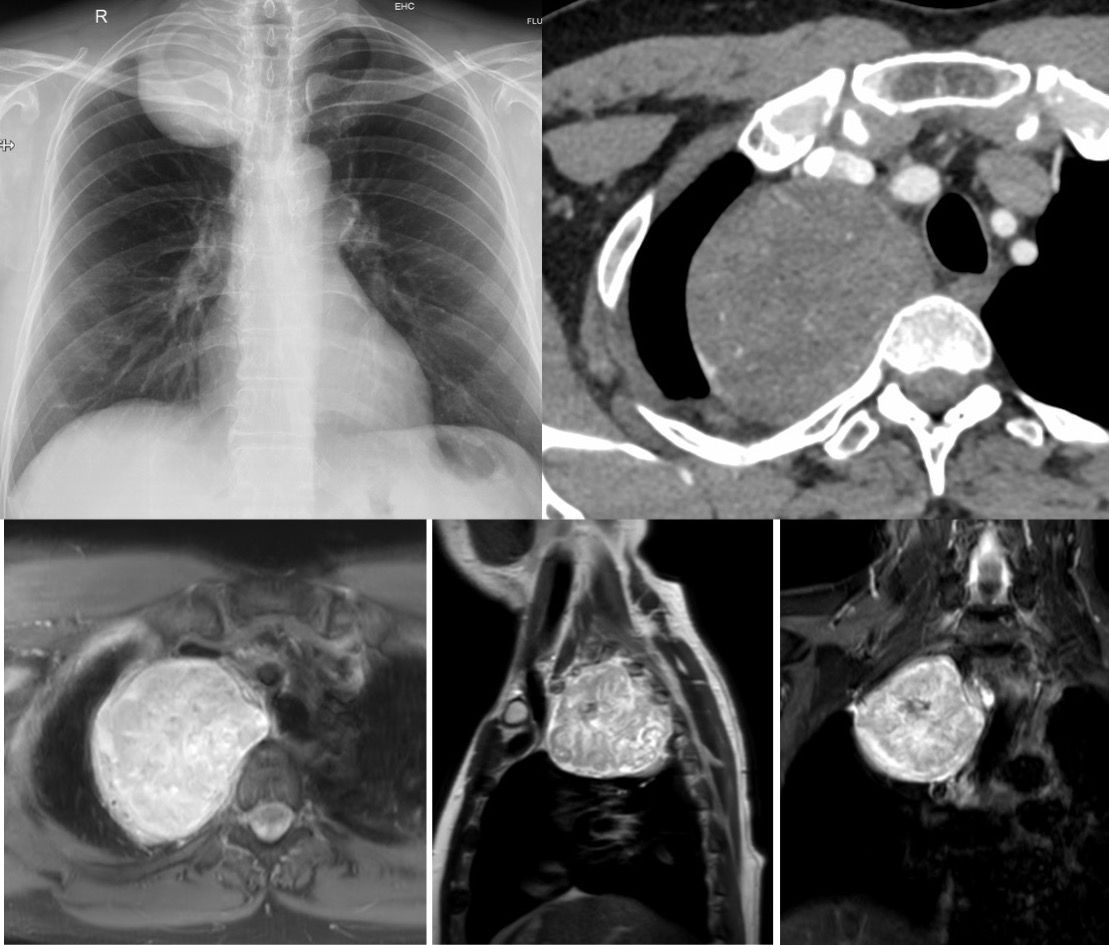

Case 80: Upper Posterior Paravertebral Mass Members Public

The differential of an upper posterior paravertebral mass is short and limited